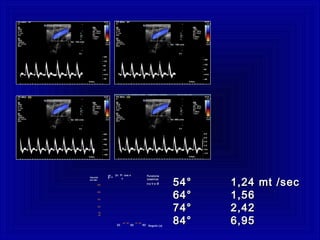

Angolo (ø)

Velocità

cm/ sec

30 60 90

40° 50°

60

50

250

200

150

100

70° 80°

FunzioneFunzione

cosenicacosenica

tra V etra V e øø

2v Fi cos ø

cF=

Misurazione

Si sempre Attenzione

< 60° > 60°

54° 1,24 mt /sec54° 1,24 mt /sec

64° 1,5664° 1,56

74° 2,4274° 2,42

84° 6,9584° 6,95Angolo (ø)